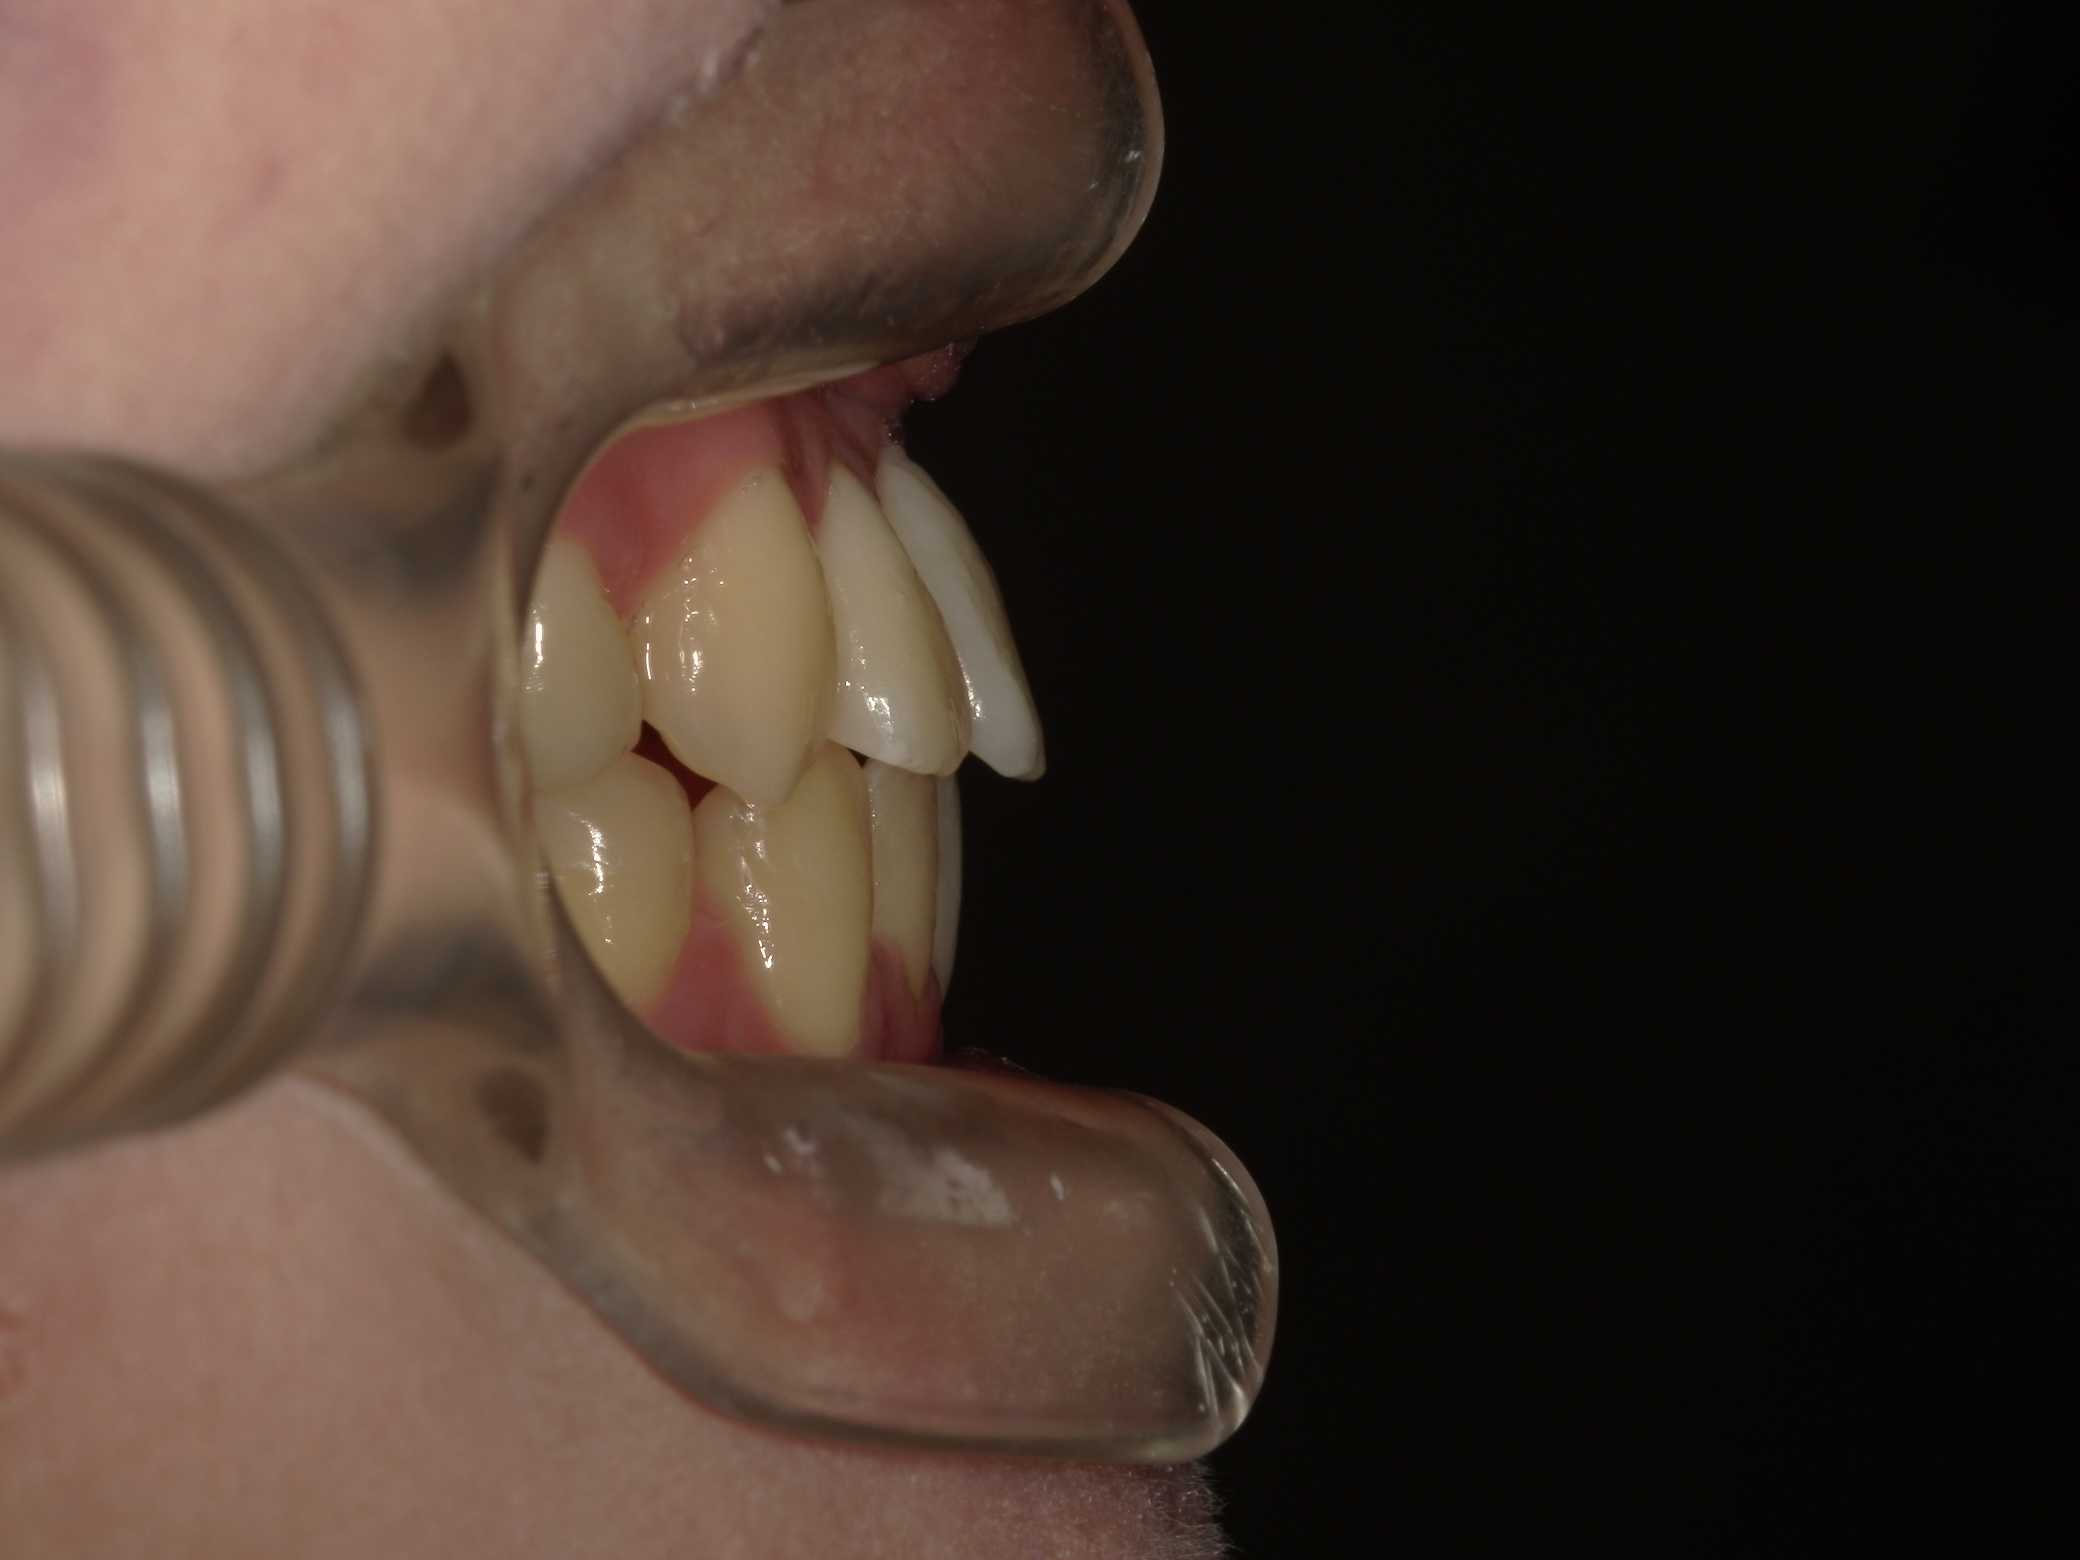

口元の突出感が気になる

| 年齢・性別 |

25歳の女性 |

|---|---|

| 主訴 | 口元の突出感を気にされて来院された。咬み合わせや審美的な改善を希望されていました。 |

| 治療期間・回数 | 3年6ヶ月・30回 |

| 費用 | 1,000,000円 |